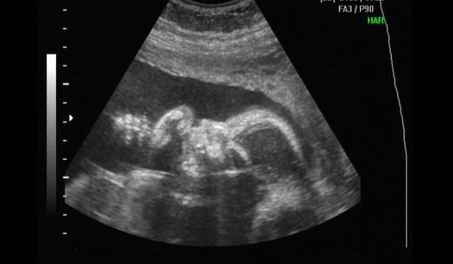

Mégsem múlt héten voltam dokinál, mert elmaradt a rendelés örültem....Így tegnap voltam dokinál minden rendben, meg du. 4D-n voltunk. Tényleg fiú és jó nagy a korához képest,több, mint egy héttel nagyobb 860 gr. :D Majd próbálok kivenni a videóból képet.